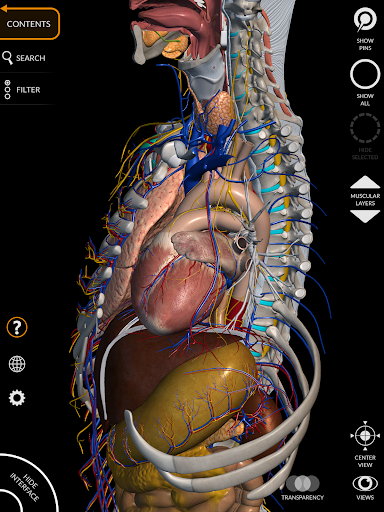

"Anatomy 3D Atlas" дозволяє легко та інтерактивно вивчати анатомію людини.

Завдяки простому та інтуїтивно зрозумілому інтерфейсу можна спостерігати кожну анатомічну структуру під будь-яким кутом.

Анатомічні 3D-моделі особливо деталізовані та мають текстури з роздільною здатністю до 4k.

Поділ за регіонами та попередньо визначені види полегшують спостереження та вивчення окремих частин або груп систем і зв’язків між різними органами.

АНАТОМІЧНІ 3D МОДЕЛІ

• Кістково-м’язова система

• Серцево-судинна система

• Нервова система

• Простий та інтуїтивно зрозумілий інтерфейс

• Обертайте та збільшуйте кожну модель Тривимірний простір

• Можливість приховування або ізоляції однієї чи кількох вибраних моделей

• Фільтр, щоб приховати або відобразити кожну систему

• Функція прозорості

• Візуалізація м’язів через рівні шарів від поверхневих донизу до найглибших